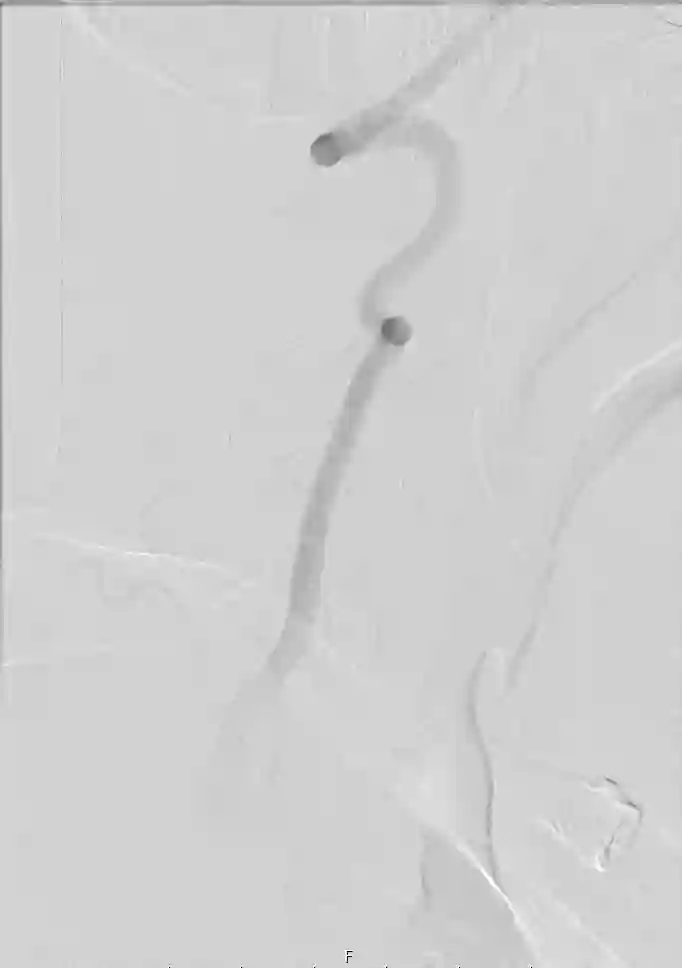

Der Goldstandard zur optimalen Darstellung der Arteria vertebralis ist die digitale Subtraktionsangiographie, kann jedoch je nach klinischer Fragestellung auch in der CT-Angiographie oder MRT Bildgebung dargestellt wird.

Im Bereich der Arteria vertebralis können typischerweise Dissektionsaneurysmen auftreten und eine Subarachnoidalblutung verursachen[^3]. Die Behandlung dieser Dissektionsaneurysmen kann je nach Fall beispielsweise endovaskuläre mithilfe von Implantation eines Flow-Diverters behandelt werden[^4] [^5].